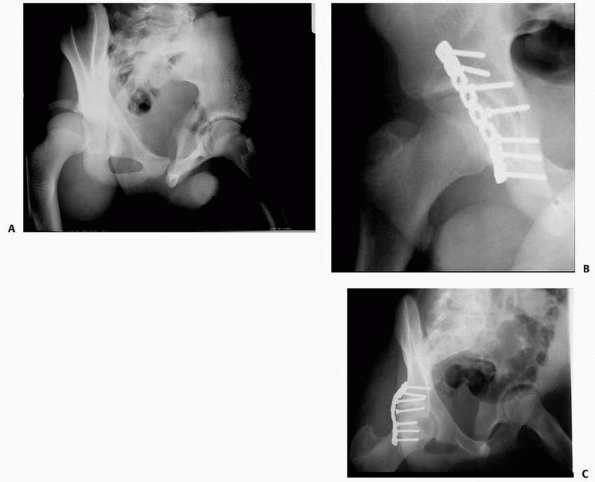

loss.36 Internal fixation with anterior pubic symphysis plating and percutaneous sacroiliac screw fixation may be required.36 Stiletto84 (Fig. 20-19)

reported good results after open reduction and internal fixation of

unstable pelvic fractures in two toddlers. AO small-fragment

FIGURE 20-19 This radiographic series highlights treatment of the unstable pelvic fracture with hemodynamic instability. A.

Anteroposterior pelvis radiograph of a 12-year-old male who was a pedestrian hit by a car. There is a wide symphysis and a displaced fracture adjacent to the left sacroiliac joint. The towel clips seen on radiograph are to hold a sheet (sling) around the pelvis to help temporarily control hemorrhage. B. CT scan showing the displaced posterior injury. C. Pelvis radiograph after an anterior external fixation was placed urgently to stabilize the pelvis. This along with resuscitation stabilized the hemodynamic status. D. Once the patient had stabilized, the external fixation was converted to anterior internal fixation with a plate on the symphysis pubis and the posterior instability was treated with a sacroiliac screw. |